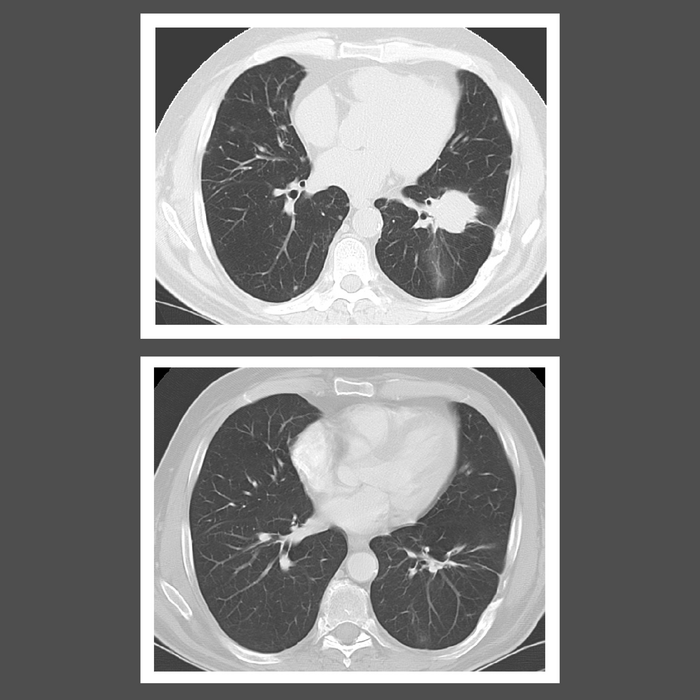

LYG scans (IMAGE) NIH/National Cancer Institute Caption LYG scans Credit National Cancer Institute Usage Restrictions none License Original content Disclaimer: AAAS and EurekAlert! are not responsible for the accuracy of news releases posted to EurekAlert! by contributing institutions or for the use of any information through the EurekAlert system.